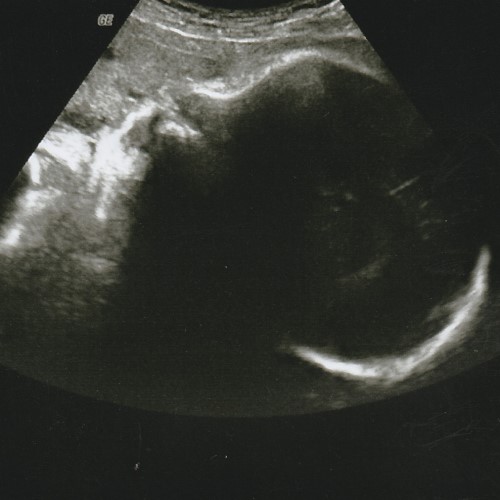

My second pregnancy came with an early scare at 6 weeks. I had a considerable amount of brown spotting which made me panic and saw me going to the hospital for an early scan. (Tip: Take a photo of any spotting and show it to the hospital staff. I realised that everyone’s measurement of ‘a little’ or ‘a lot’ is different. A picture would be clearer for diagnosis. ) Thankfully, baby was alright and it was not the big M word. I was however advised to rest more and take care. No more carrying of heavy things. That was a little tough coz 3-year-old Emilee still asked to be carried. We just told her that mummy wasn’t well and doctor said I couldn’t carry her. She whined a bit at first but she soon settled into the new adjustment.